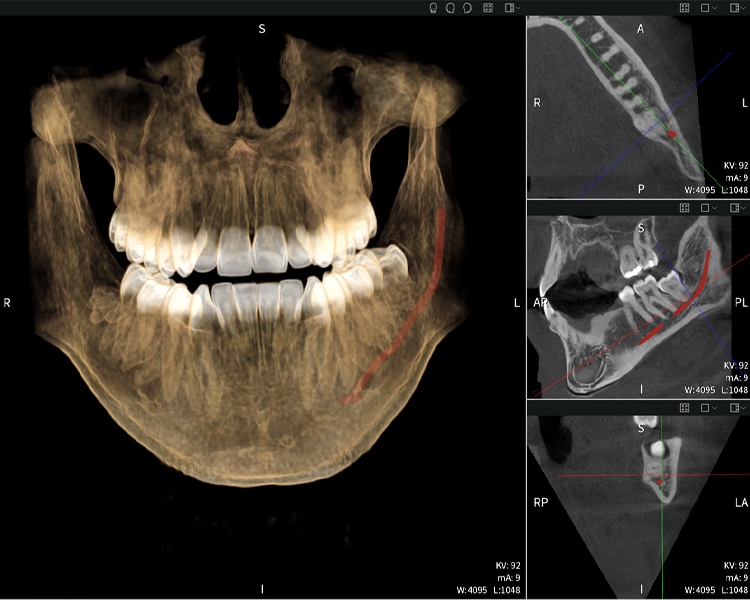

Figures b–d show various views of a 3D reconstruction of the mandible, providing a comprehensive overview of the mandibular anatomy, the position of the nerves in relation to the teeth, and allowing assessment of tooth symmetry and alignment.

Figure c: Imaging results of Seethrough Max, in front of a black background.

Figure c